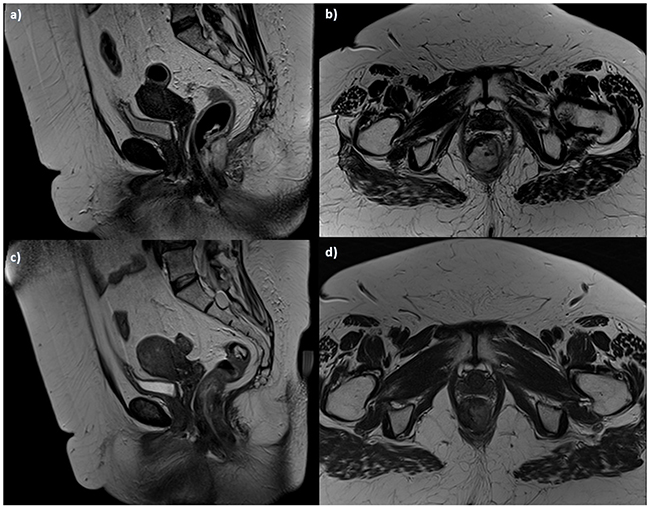

When we analyzed the residual anal tissue after treatment, we found no significant difference in EUS assessment and T2-W SI between pre and post treatment both for responders (p = 0.11 at Wilcoxon test) and for non responders patients (p = 0.32 at Wilcoxon test) (Figure 3): residual cancer and fibrosis showed similar hypoechoic appearance and hyperintense signal. Conversely we found significant difference in dynamic study with correlate inspective analysis of TIC (type 2, slow sustained enhancement), in SI of DWI (less restriction of water diffusion with less hyperintensity in b800 s/mm2) and of ADC map (less hypointensity) and ADC values (1220x10-3 mm2/s; range 910-1310x10-3 mm2/s) between pre and post treatment for responders patients (p = 0.02, 0.03, 0.001,0.003 respectively at Wilcoxon test) (Figure 4 and Figure 5). While for non-responders patients TIC, SI of DWI and ADC map and ADC values not showed significant differences between pre and post treatment (p = 0.23 at Wilcoxon test).

Figure 3. Woman 54y, anal cancer. TSE T2-W in sagittal a. and axial b. plane, pre-treatment morphological assessment: the lesion infiltrates internal and external sphincters. Post treatment assessment: TSE T2-W images in sagittal c. and axial d. plane show tumor size reduction, with residual tissue.